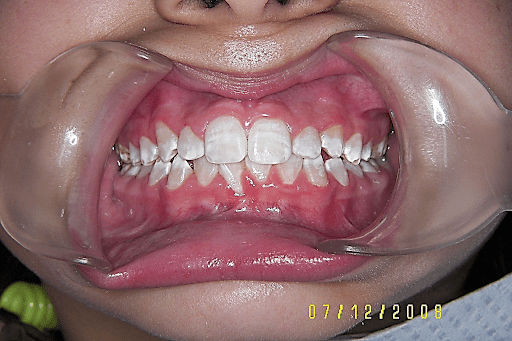

Test for labial frenum surgery